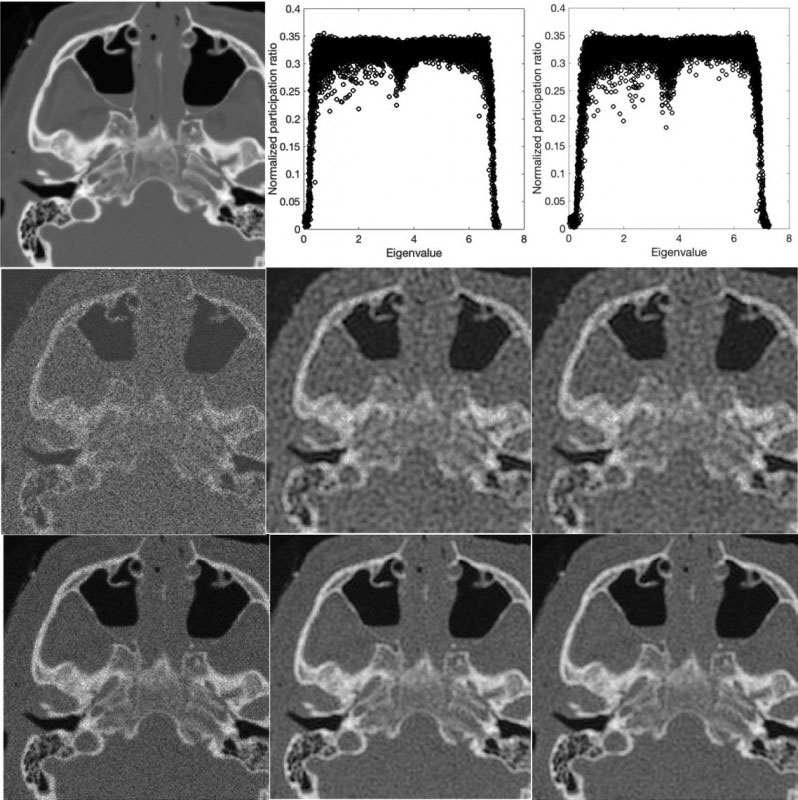

A central concept in the math describing matter and energy, localization is used to explain how particles vibrate in a space. Vibrations that stay confined are considered localized, while vibrations that spread out are diffused. Similarly, pixel intensity, or brightness, in a clear image can be considered localized, while noisy patterns in an image can be considered diffused.

The authors apply the same mathematics that describes the localization of particle vibrations in the surrounding physical space to decipher the localization of pixel intensity in images. In this way, they can separate the noise-free “signal” of the anatomical structures in the image from the visual noise of stray pixels.

“The main aspect was developing an algorithm that automatically separates the localized (signal) and nonlocalized (noise) components of pixels in an image by exploiting their distinct behaviors,” Hashemi said.